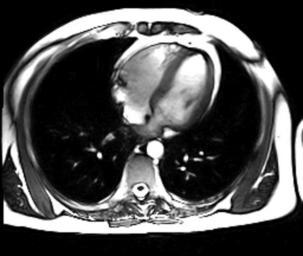

MAKE A MEME View Large Image Beating Heart axial.gif Movie GIF format of a beating heart obtain using a 3T MRI scanner Single slice along the axis of the subject G D Clarke 2007-05-24 G D Clarke This is an image of me obtained and owned by me Magnetic resonance imaging ...

Keywords: Beating Heart axial.gif Movie GIF format of a beating heart obtain using a 3T MRI scanner Single slice along the axis of the subject G D Clarke 2007-05-24 G D Clarke This is an image of me obtained and owned by me Magnetic resonance imaging of the heart